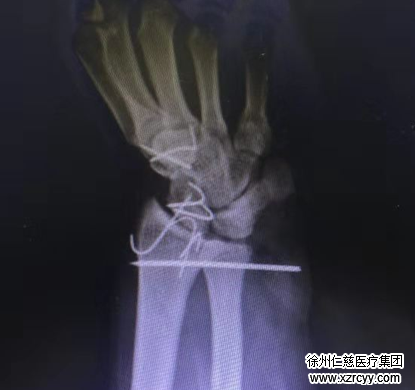

吻合血管,修复断裂的肌腱、韧带,固定骨折部位……一切都在紧张而有序的进行着,然而,伤势的复杂程度决定了手术不可能一切顺利。

当唐洪伟医生吻合断裂的血管后,一次通血成功,唐医生刚刚松口气准备修复下一处时,突然发现患者因为之前失血过多,血压持续降低,导致毛细血管反应迟缓,原本通血成功的血管竟突然没有血运了。经重新探查血管后医生发现,患者离断肢体血管远端广泛栓塞,这是让大家万万没有想到的,但唐医生没有放弃,从患者小腿取下15公分的血管进行移植,桥接血管,最终离断肢体顺利通血,完美成活。

就这样,唐洪伟医生手术小组整整用了9小时,将患者完全离断的肢体成功再植,为高翔保住了左手。